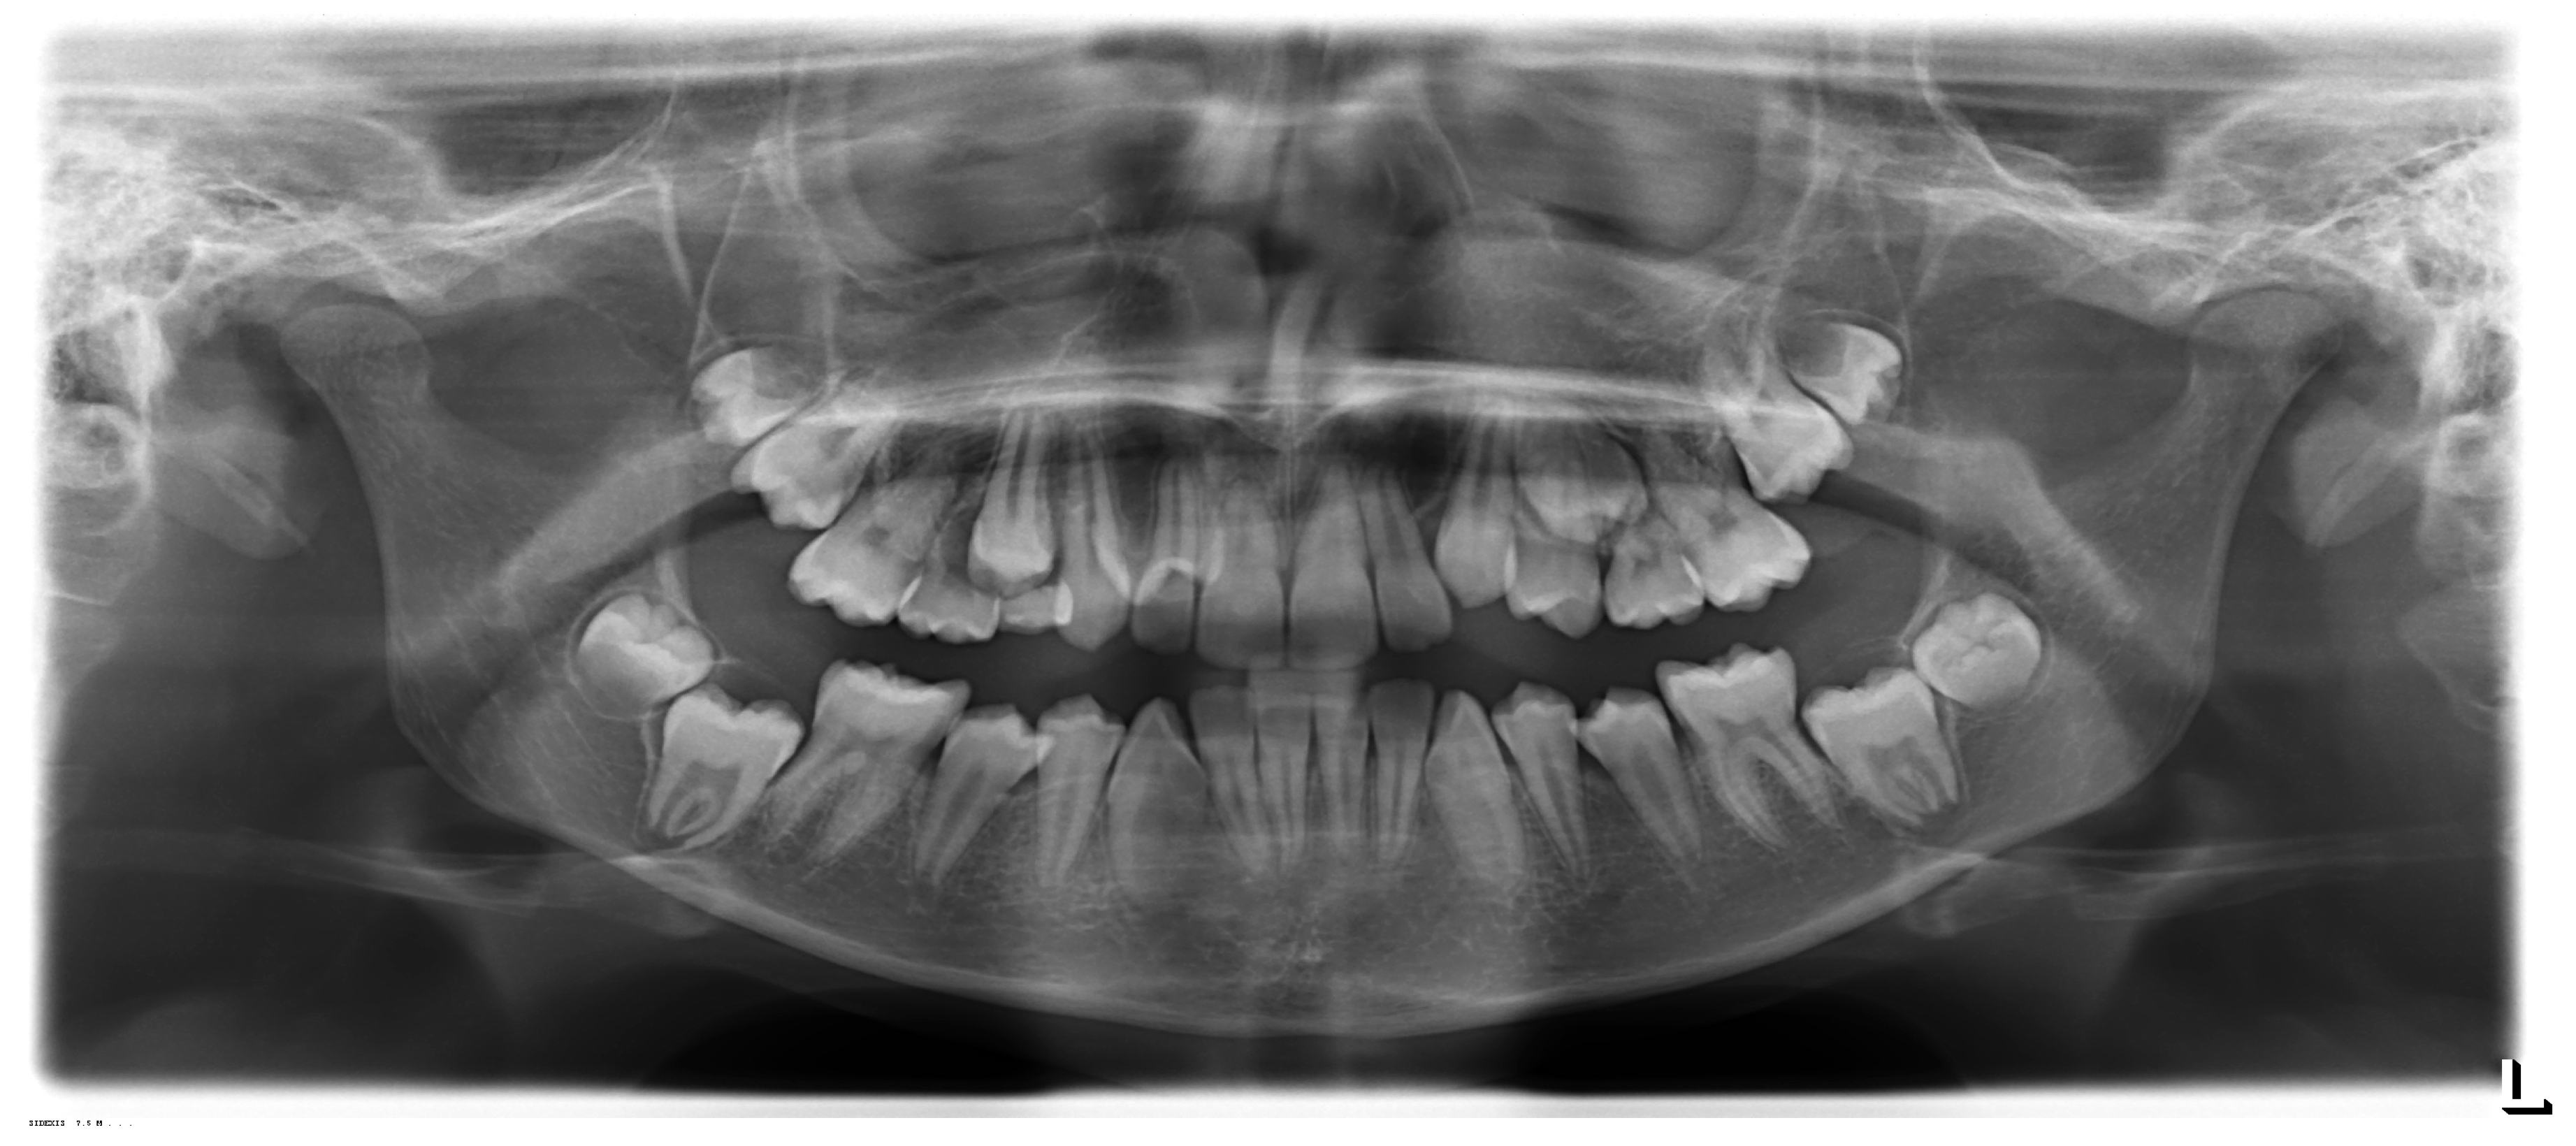

How to Manage Impacted Third Molars: Germectomy or Delayed Removal? A Systematic Literature Review

1. Introduction

3.3. Characteristics of Participants

3.4. Characteristics of Interventions